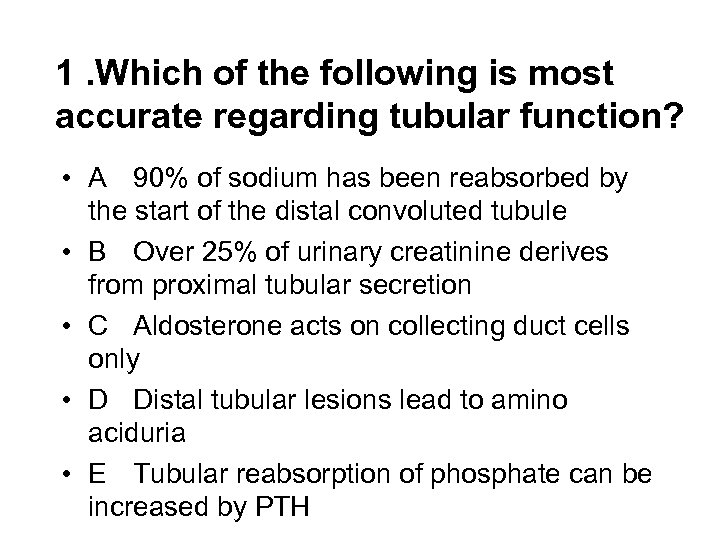

1. Which of the following is most accurate regarding tubular function? • A 90% of sodium has been reabsorbed by the start of the distal convoluted tubule • B Over 25% of urinary creatinine derives from proximal tubular secretion • C Aldosterone acts on collecting duct cells only • D Distal tubular lesions lead to amino aciduria • E Tubular reabsorption of phosphate can be increased by PTH

1. Which of the following is most accurate regarding tubular function? • A 90% of sodium has been reabsorbed by the start of the distal convoluted tubule • B Over 25% of urinary creatinine derives from proximal tubular secretion • C Aldosterone acts on collecting duct cells only • D Distal tubular lesions lead to amino aciduria • E Tubular reabsorption of phosphate can be increased by PTH

1. Which of the following is most accurate regarding tubular function? • A 90% of sodium has been reabsorbed by the start of the distal convoluted tubule • B Over 25% of urinary creatinine derives from proximal tubular secretion • C Aldosterone acts on collecting duct cells only • D Distal tubular lesions lead to amino aciduria • E Tubular reabsorption of phosphate can be increased by PTH

1. Which of the following is most accurate regarding tubular function? • A 90% of sodium has been reabsorbed by the start of the distal convoluted tubule • B Over 25% of urinary creatinine derives from proximal tubular secretion • C Aldosterone acts on collecting duct cells only • D Distal tubular lesions lead to amino aciduria • E Tubular reabsorption of phosphate can be increased by PTH